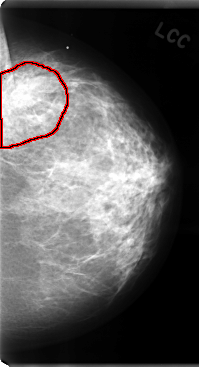

C_0080_1.LEFT_CC

LEFT_CC LINES 4760 PIXELS_PER_LINE 2576 BITS_PER_PIXEL 12 RESOLUTION 50 OVERLAY

FILE: C_0080_1.LEFT_CC.OVERLAY

TOTAL_ABNORMALITIES 1

ABNORMALITY 1

LESION_TYPE MASS SHAPE IRREGULAR MARGINS ILL_DEFINED

ASSESSMENT 4

SUBTLETY 4

PATHOLOGY MALIGNANT

TOTAL_OUTLINES 1

BOUNDARY